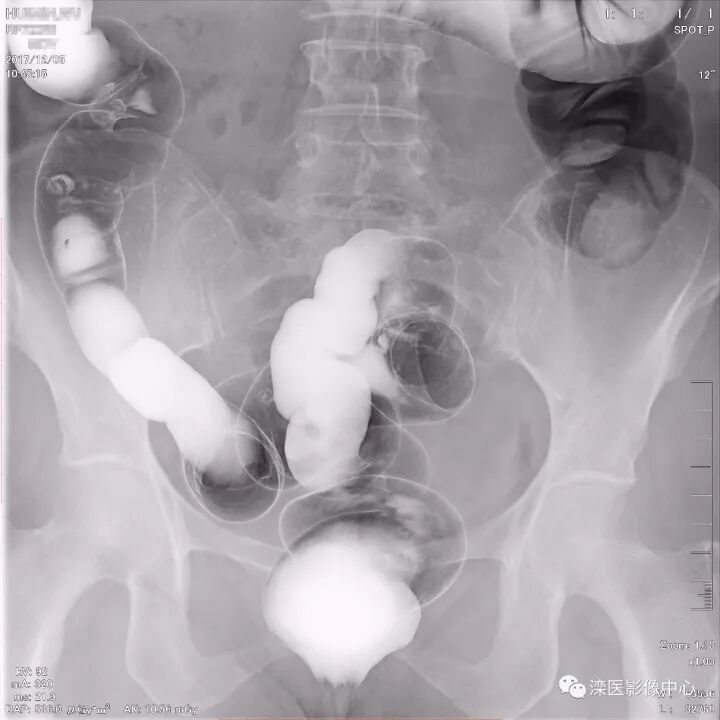

下面请您审阅近期我院影像科开展下消化道双对比造影检查的图像:

(以上图像多角度显示直肠、乙状结肠)